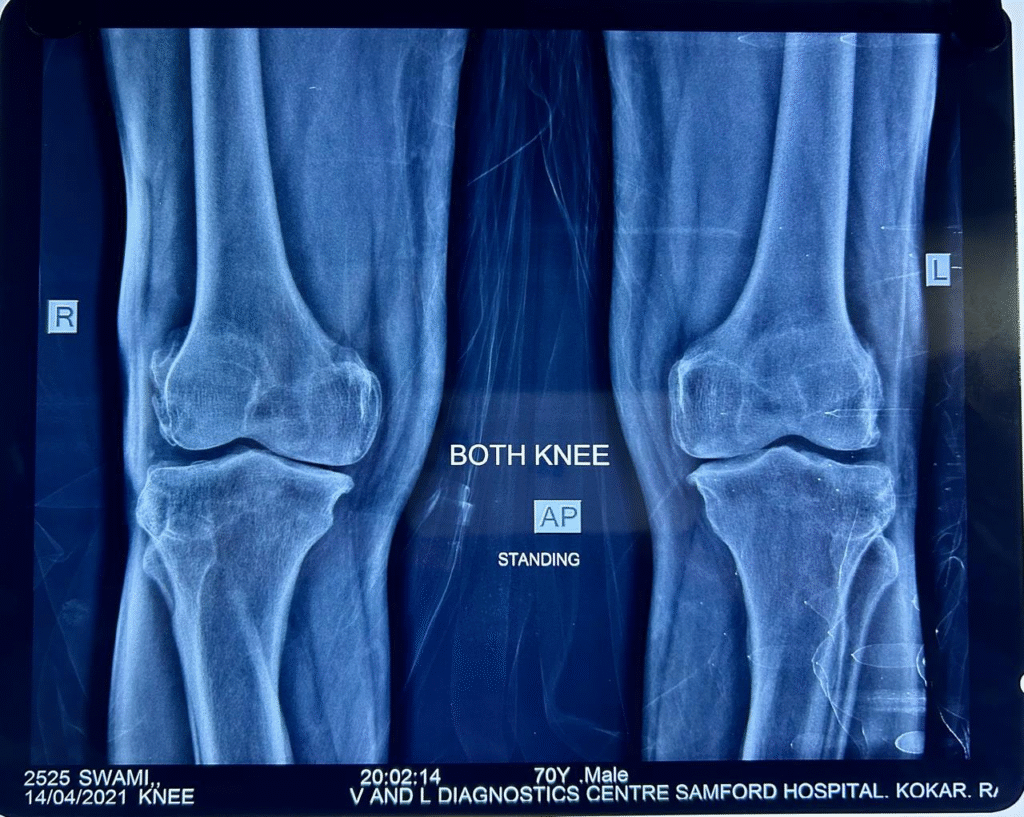

Recent X-ray (dated 14/4/2021) shows no further progression of OA.

April 2021